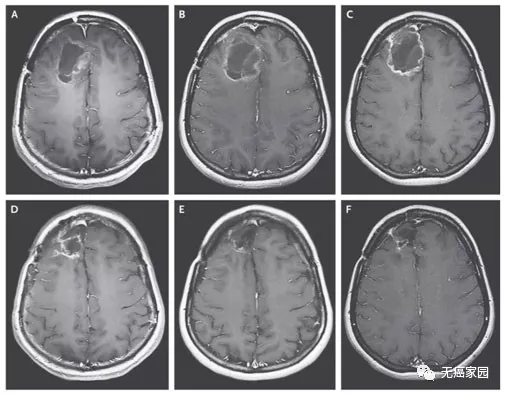

知名癌症杂志《cancerdiscovery》,报道了NVL-520在一例患IV期肺腺癌和多发性脑转移的65岁患者中,引发了客观肿瘤反应。该例患者循环肿瘤DNA(ctDNA)检测,发现了EZR-ROS1。在接受恩曲替尼(Entrectinib)治疗伊始,有初步反应,但9个月后病情出现进展。复查发现EZR-ROS1融合,并确定了ROS1G2032R突变。患者随即开始接受卡铂、培美曲塞、贝伐珠单抗、恩曲替尼联合治疗。但不幸的是,效果不佳,患者脑转移不断增长,并出现了新的肝脏转移。患者在入组后,接受NVL-520治疗,结果显示:

1、在治疗第4周,肝脏和肺部的几个转移灶减少(根据RECIST1.1,减少38%);右枕叶转移灶消退;EZR–ROS1和ROS1G2032R等位基因频率降低。

2、在治疗5个月左右,患者达到部分缓解(PR),大脑和肝脏的疾病进一步消退(RECIST1.1为-58%),且截止到数据统计时,未报告神经毒性(详见下图)。

图1该患者接受NVL-520治疗前后,影像学对比图

▲图源“cancerdiscovery”,版权归原作者所有,如无意中侵犯了知识产权,请联系我们删除

注:

①CT(上)图中的蓝色箭头,表示5/6段和3段肝转移,在治疗过程中持续消退。

②MRI(下)图中的蓝色箭头表示右枕叶转移,该转移在第4周时尺寸减小,并在第16周时变得几乎不可察觉。

综上,患有EZR-ROS1融合阳性肺腺癌,且具有ROS1G2032R耐药突变的患者,在接受恩曲替尼(Entrectinib)和化疗后,证实对NVL-520有PR。